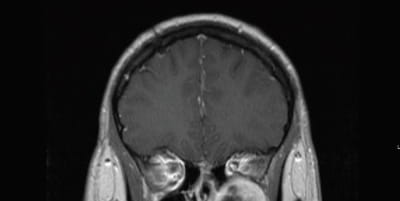

Dr. Rodriguez was presented with such a case in April 2015 – a young man with NF-2 who’d previously had surgery at another hospital to remove one of his bilateral acoustic neuromas. The patient complained of left facial pain and pressure, nasal airway obstruction, decreased sense of smell and epistaxis. Imaging demonstrated a left infratemporal fossa/pterygopalatine fossa mass, consistent with a schwannoma.

“It had remodeled the medial wall of the pterygopalatine fossa and floor of the orbit,” Dr. Rodriguez says. “It had expanded posteriorly to be lateral to the left sphenoid sinus at the base of the temporal lobe.”

“Although the lesion appeared radiographically benign, it was likely going to continue to slowly grow over time and cause progression of symptoms,” Dr. Rodriguez says. “What makes these tumors very interesting is that they slowly expand and can displace normal structures. Given the proximity to his orbit, he could begin to experience double vision as his eye was slowly displaced superiorly. There was also a small chance of the lesion degrading into malignancy.”